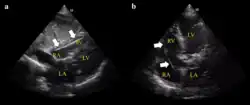

- Example of ECG off the device a) free floating in the RV b) in contact with the RV wall